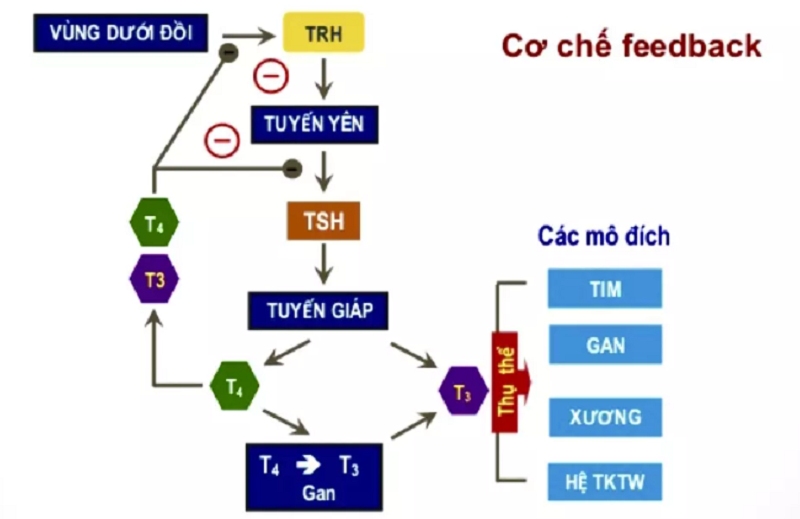

Cơ thể không sản xuất T3 theo một nguồn duy nhất. Tuyến giáp chỉ tiết ra 10–20% lượng T3, còn lại 80–90% được tạo ra từ T4 trong các mô như gan, não và cơ thông qua enzyme deiodinase. Cơ chế này đã được mô tả chi tiết trong nghiên cứu sinh lý học kinh điển của Bianco và cộng sự (2002), qua đó cho thấy mỗi loại deiodinase (D1, D2, D3) có vai trò riêng: D1 tham gia chuyển đổi T4 → T3 trong máu, D2 tạo T3 ngay tại mô cần thiết (như não), còn D3 bất hoạt hormone để tránh dư thừa.

T3 tạo ra từ chuyển đổi T4

Ngoài lượng T3 do tuyến giáp tiết ra, cơ thể còn tạo ra phần lớn T3 thông qua quá trình chuyển đổi T4 thành T3 nhờ enzym deiodinase. Khoảng 80% T3 được tạo ra theo cơ chế này, vì vậy sức khỏe của gan, thận và các mô ngoại biên có ảnh hưởng lớn đến nồng độ T3 toàn cơ thể. Khi cơ thể rơi vào tình trạng stress nặng, nhiễm trùng hoặc suy dinh dưỡng, khả năng chuyển đổi T4 → T3 giảm mạnh như một cách tiết kiệm năng lượng.

Khi T3 nằm trong giới hạn bình thường, các chức năng như sản xuất năng lượng, điều hòa nhịp tim, tiêu thụ oxy và duy trì thân nhiệt diễn ra ổn định. Điều này cho thấy trục tuyến yên – tuyến giáp hoạt động hài hòa, đồng thời gan và thận chuyển đổi T4 → T3 hiệu quả.

Ngược lại, khi T3 giảm thấp, tốc độ trao đổi chất chậm lại khiến cơ thể dễ mệt mỏi, lạnh, tăng cân và phản xạ chậm hơn. Trong các tình trạng stress nặng như nhiễm trùng, phẫu thuật hay suy dinh dưỡng, quá trình chuyển đổi T4 → T3 bị ức chế, dẫn đến hội chứng Low T3 – đây là phản ứng tự nhiên nhằm tiết kiệm năng lượng. Nhiều bệnh nhân nặng có T3 thấp nhưng TSH vẫn bình thường, thể hiện sự thích nghi của cơ thể. Trong các trường hợp này, điều trị T3 trực tiếp hiếm khi được khuyến nghị, mà cần tập trung cải thiện bệnh nền.

Ngoài ra, có những trường hợp T3 tổng bình thường nhưng triệu chứng tuyến giáp vẫn rõ rệt. Điều này có thể xảy ra khi Free T3 thấp do rối loạn chuyển đổi T4 → T3 hoặc bất thường trong vận chuyển hormone. Vì vậy, để đánh giá chính xác chức năng tuyến giáp, cần xem xét đồng thời bộ ba chỉ số TSH – Free T4 – Free T3 thay vì chỉ dựa vào T3 đơn lẻ.